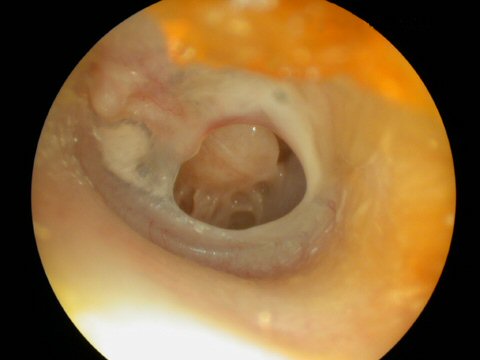

Acute Infection with bulging of the tympanic membrane due to pressure from purulence (pus) behind it. The last picture reveals an ear tube that has gotten prematurely blocked and the ear is once again infected.

Ear tubes - The first picture shows an ear tube that has fallen out but is stuck to ear canal by ear wax. The last picture shows a T-tube, these stay in place much longer but run the risk of leaving a permanent perforation when finally removed.